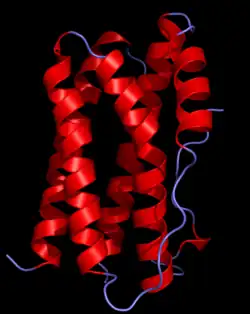

| chemokine receptors |

|

Seven transmembrane helix, rhodopsin-like receptor[3] | G protein-coupled |